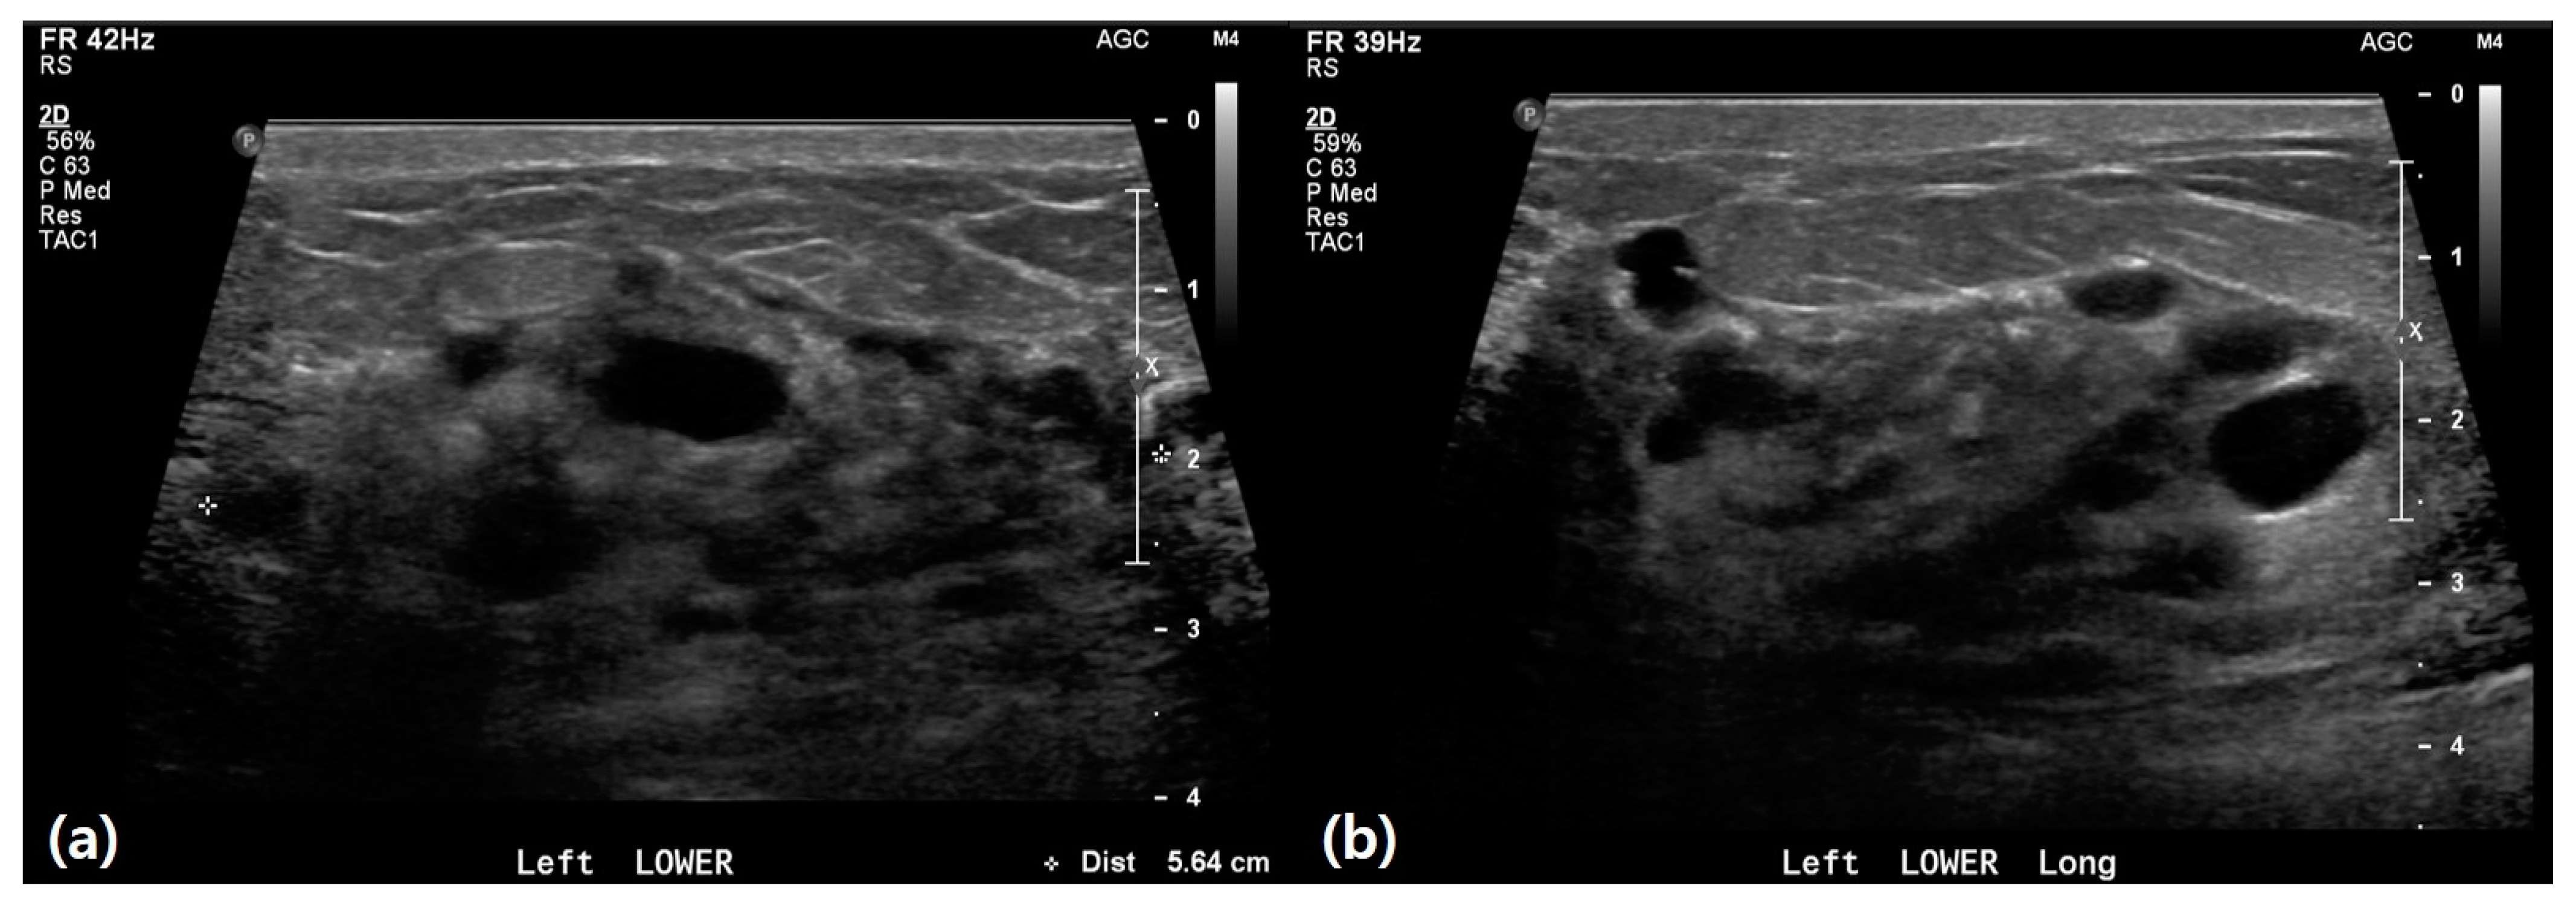

3.2. Ultrasound Features